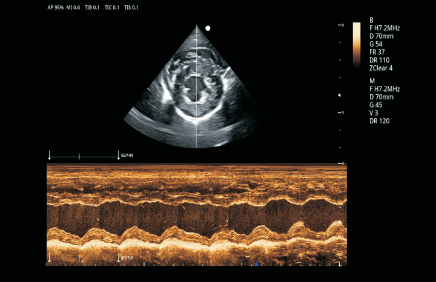

VU60搭载了全新的焕影成像技术平台,采用uSeed全新的CPU+GPU+FPGA硬件架构,多核并行处理技术,搭载高性能单晶体探头和复合晶体探头,可提供更宽带宽、更好穿透力和分辨率的超声影像,精准高效,全面提升临床诊断信心。

卓越的图像质量